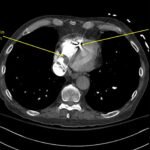

A 78-year-old gentleman presented to the emergency department (ED) for palpitations and dizziness. He had a complicated medical history including atrial fibrillation (AF), recently status post a Watchman procedure, oxygen-dependent chronic obstructive pulmonary disease (COPD), and heart failure with preserved ejection fraction (HFpEF). Point-of-care ultrasound (POCUS) revealed the presence of an intracardiac right atrial thrombus. Computed tomography (CT) angiography confirmed the presence of multiple pulmonary emboli (PE), and extension of the thrombus into the inferior vena cava. Pulmonary emboli are a common complication of thrombus in the right atrium. Management may include anticoagulation, thrombolysis, or thrombectomy. This case highlights that emergency physicians can expedite the diagnosis of intracardiac thrombus by using POCUS. The case presented describes a medically complex patient presenting with symptomatic right intracardiac and inferior vena caval thrombosis complicated by multiple PE. Point-of care ultrasound of the heart and lungs were included in his initial assessment, revealing findings of an intracardiac thrombus, and ruling out multiple other differential diagnoses including pericardial tamponade, pleural effusion, pulmonary edema, and pneumothorax. This finding changed the trajectory of this patient’s evaluation and management, and demonstrates the important role of POCUS in the care of ED patients with undifferentiated cardiopulmonary symptoms.